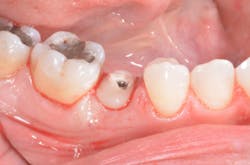

The patient took 2 g amoxicillin 45 minutes before the appointment, and a preoperative rinse with 0.12% chlorhexidine mouthwash was used prior to surgery. The patient was given right inferior alveolar nerve and long buccal nerve blocks, as well as No. 29 buccal and lingual infiltration with 2% lidocaine and 1:100,000 epinephrine. Next, No. 29's retained root was extracted with minimal trauma using a periotome (figure 7).

The surgical guide was placed, and a full seat was observed with good stability (figure 8A). The osteotomy site was prepared using serial drills per manufacturer’s recommendation (figure 8B).